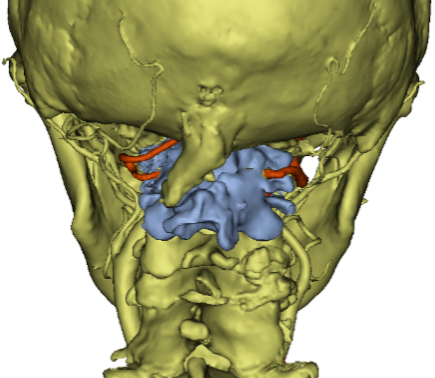

椎动脉走行变异,解剖结构紊乱

朱超主任介绍,上颈椎又称寰枢椎,指第一、二颈椎,是连接大脑与躯干的关键部位,其结构复杂、活动灵活,承担着支撑头部、保护神经及血管的重要使命。由于发育、炎症、外伤等多种因素,寰枢关节可能发生脱位,导致脊髓神经受压,患者可出现神经元损害的表现,严重时可出现高位截瘫。由于该区域解剖结构复杂,手术难度大、风险高,稍有不慎可能损伤椎动脉、脊髓等重要结构,导致出血、瘫痪乃至死亡等灾难性后果。进一步检查发现,陈阿婆的椎动脉迂曲、变异,走行在侧块的正后方,还要在增生的瘢痕区域进行手术,继发损伤的风险极高。

骨科主任、脊柱外科主任沈洪兴组织了详尽的术前讨论,并与手术室、麻醉科、重症监护室等多科室紧密合作,共同为陈阿婆制定了一份周密的手术计划:先进行为期一周的术前颅骨牵引准备,再进行手术复位。在沈洪兴主任的指导下,手术由朱超主刀,使用大重量牵引技术,向上推开椎动脉,巧妙翘拨复位寰枢关节,并借助机器人辅助导航系统,精准植入固定装置,既实现了寰枢关节的精确复位,又保护了椎动脉和脊髓神经。